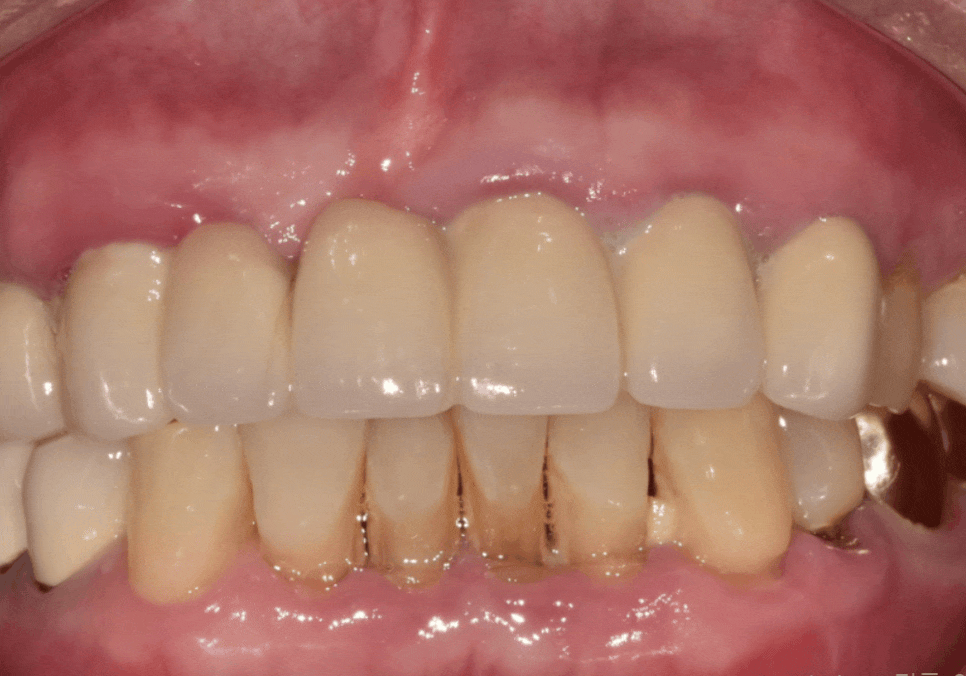

이제 임플란트 보철을 만들기 위해

본을 뜹니다.

앞니는 인상을 결정하는

가장 중요한 부위인 만큼

심미적인 완성도가 무엇보다 중요한데요.

저희는 치과 내부에서

기공소를 직접 운영하고 있어,

보철 담당 기공사가 환자분의 주변 치아

색상과 투명도,형태를 실시간으로 직접 확인하며

제작합니다.

앞니 보철물은 미세한 차이로도

전체적인 인상이 달라질 수 있는데요.

완성된 지르코니아 보철물을 보니

주변 치아와 아주 자연스럽게 어우러지는

만족스러운 결과가 나온 것 같습니다.^^